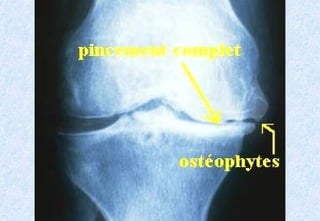

Radiographie standardRadiographie standard ::

IncidencesIncidences ::

-Face debout en extension ou en position de Schuss.Face debout en extension ou en position de Schuss.

-Profil debout en flexion.Profil debout en flexion.

RésultatsRésultats ::

-Pincement de l’interligne articulaire.Pincement de l’interligne articulaire.

-Condensation sous-chondrale du plateau tibial.Condensation sous-chondrale du plateau tibial.

-Géodes sous chondrales (rares).Géodes sous chondrales (rares).

-Ostéophytes (condyles fémoraux plateaux tibiaux, épines tibiales).Ostéophytes (condyles fémoraux plateaux tibiaux, épines tibiales).

Dans la gonarthrose évoluée :Dans la gonarthrose évoluée :

-Enfoncement cupuliforme des plateaux tibiaux.Enfoncement cupuliforme des plateaux tibiaux.

Il n’existe pas de parallélisme radio-clinique.

Arthrose fémoro-tibiale.Arthrose fémoro-tibiale. RadiographiestandardRadiographie standard :: IncidencesIncidences :: -Face debout en extension ou en position de Schuss.Face debout en extension ou en position de Schuss. -Profil debout en flexion.Profil debout en flexion. RésultatsRésultats :: -Pincement de l’interligne articulaire.Pincement de l’interligne articulaire. -Condensation sous-chondrale du plateau tibial.Condensation sous-chondrale du plateau tibial. -Géodes sous chondrales (rares).Géodes sous chondrales (rares). -Ostéophytes (condyles fémoraux plateaux tibiaux, épines tibiales).Ostéophytes (condyles fémoraux plateaux tibiaux, épines tibiales). Dans la gonarthrose évoluée :Dans la gonarthrose évoluée : -Enfoncement cupuliforme des plateaux tibiaux.Enfoncement cupuliforme des plateaux tibiaux. Il n’existe pas de parallélisme radio-clinique.